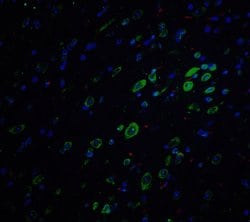

Invitrogen™ Amyloid Precursor Protein Polyclonal Antibody

Brand: Invitrogen™ PA520737

A suggested positive control is rat brain tissue lysate. PA5-20737 can be used with blocking peptide PEP-0851.

Amyloid Precursor Protein (APP) or Amyloid beta precursor protein functions as a cell surface kinesin I membrane receptor, mediating the axonal transport of beta-secretase and presenilin 1. APP is important for neurite growth, neuronal adhesion and axonogenesis. APP is a 100-140 kDa transmembrane glycoprotein that exists as several isoforms resulting from alternative splicing. Proteolytic cleavage of APP by beta- and gamma-secretases results in the generation of beta amyloid, which is the primary component of senile plaques. Senile plaques are one of the major histopathologic features of Alzheimer's disease. Abnormal regulation and processing of APP also plays a role in Down's syndrome, early onset familial Alzheimer's disease, and cerebral hemorrhage.

| Immunohistochemistry, Western Blot | |

| The immunogen is a 18 amino acid synthetic peptide within amino acids 180 - 230 of human Amyloid Precursor Protein (APP). | |

| Human, Mouse, Rat | |